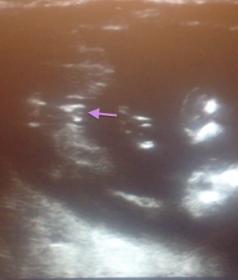

Hopefully the pictures worked this time! We have 3 beautiful boys and are hoping for our little girl :) (This US was down on the machine I have access to at school)

Girl xx

100% girl. Congrats! x

Definitely girl. I have seen this 3 times lol. Congrats!

Absolutely all girl! No doubt! Congrats :)

DEFINITE girl